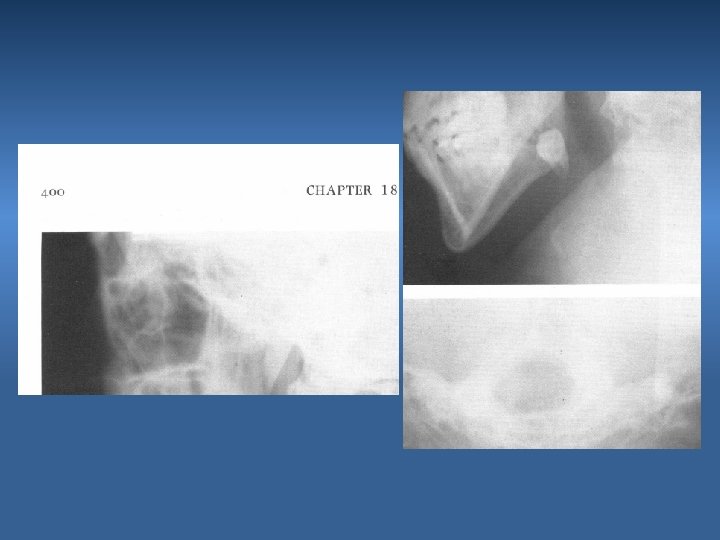

Photoelastic model of the mandible, showing the development of stress during a luxation attempt of the third molar when insufficient bone has been removed from the tooth peripherally